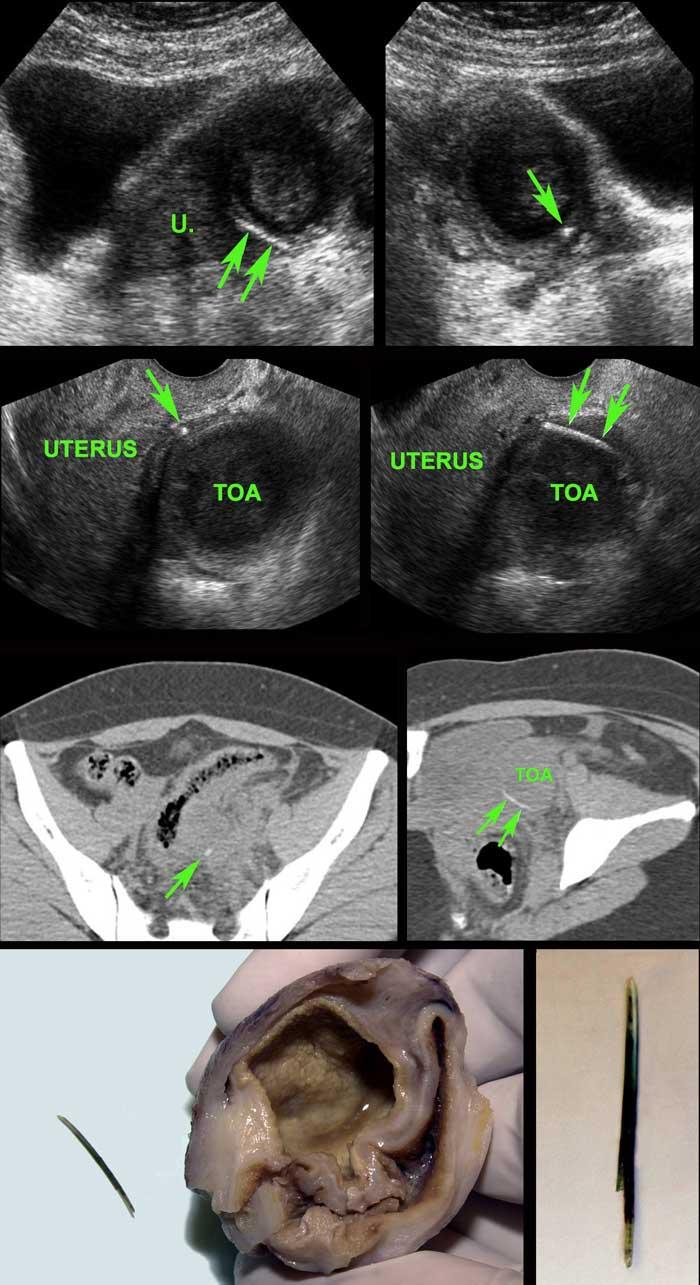

Bệnh nhân nữ người Suriname trẻ (31 tuổi) với đau hố chậu trái 3 tuần và CRP 55, nghi ngờ viêm phần phụ hoặc viêm túi thừa.

Tiền sử vỡ tử cung.

Siêu âm cho thấy khối giảm âm bên trái tử cung (u.) nghi ngờ áp xe vòi trứng-buồng trứng (TOA).

Ở ngoại vi thấy một phản âm mỏng, đường cong (mũi tên).

Siêu âm qua đường âm đạo xác nhận xương cá (mũi tên) trong thành của TOA.

CT không tiêm thuốc cản quang cho thấy TOA có liên quan mật thiết với đại tràng sigma, vốn cũng có dày thành khu trú.

Trong phẫu thuật, TOA và xương cá dính chặt vào đại tràng sigma đã được lấy ra.

Rõ ràng, xương cá sau khi xuyên thủng đại tràng sigma đã di chuyển vào buồng trứng trái, gây ra TOA.

Lưu ý màu xanh lá của xương cá, có thể do sắc tố mật.